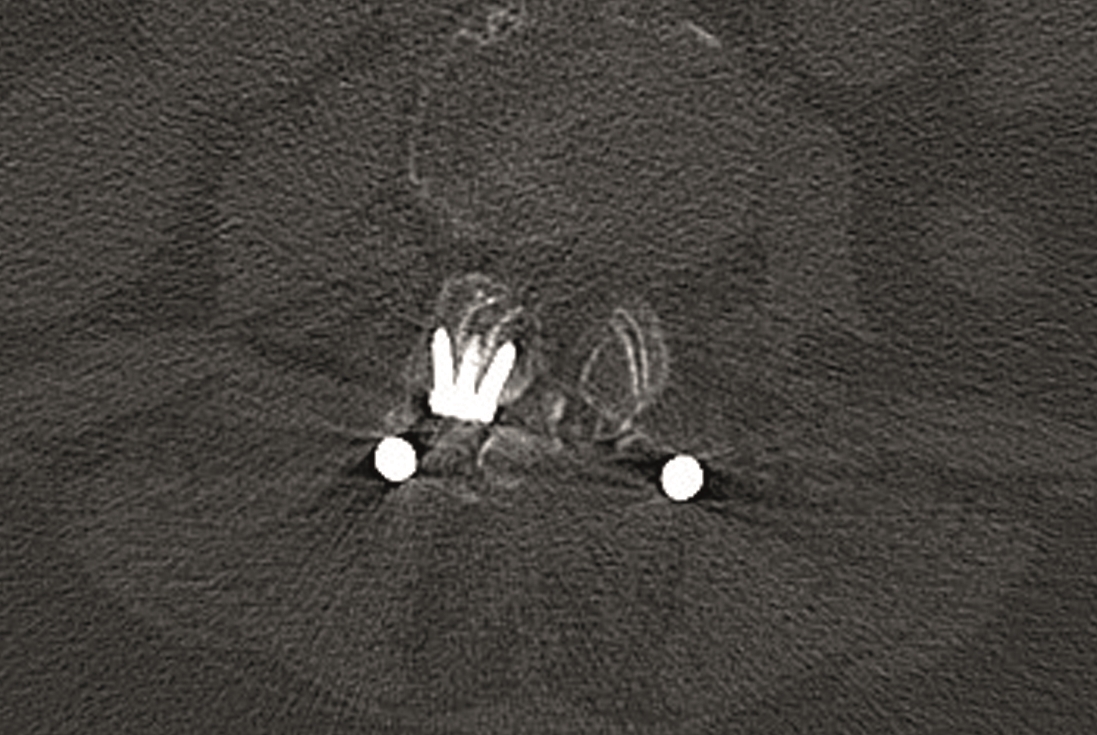

A conventional approach for posterior correction was taken, with indirect Foraminal decompression and Facet Wedge fusion (apex curve). Facet Wedge introduction after curve correction with rod in situ. X-ray follow-up initially (Fig 20), with CT assessment of Facet Wedge fusion after 6 months (Fig 21).